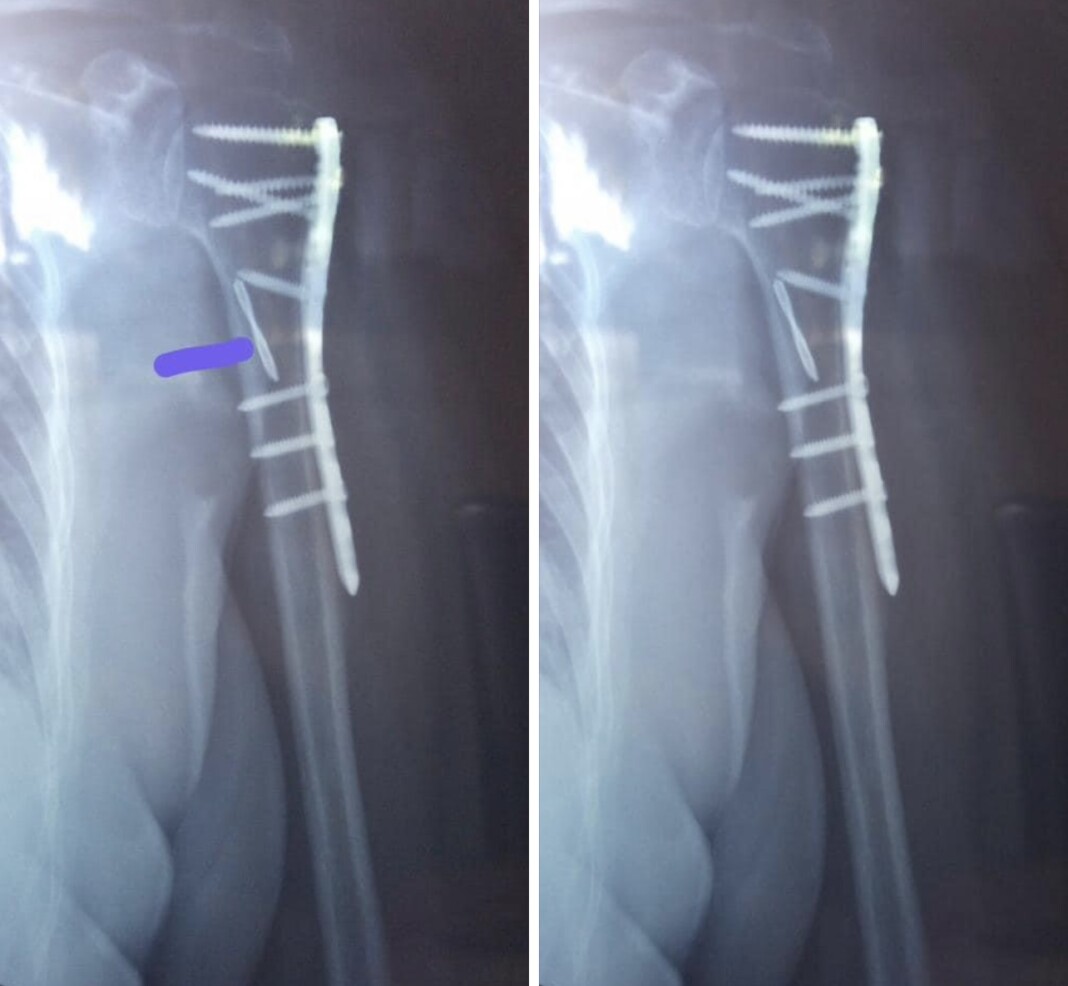

ސަރުކާރުން ހިންގާ އައިޖީއެމް ހޮސްޕިޓަލުން ކުރި އޮޕަރޭޝަނަކަށް ބޭނުން ކުރި ބުރުމާގެ ކައްޓެއް ހަށިގަނޑު ތެރޭގައި އޮތް މަންޒަރު ފެންނަ އެކްސްރޭއެއްގެ ފޮޓޯތަކެއް ސޯޝަލްމީޑިއާގައި އާއްމުވެއްޖެއެވެ.

އެ ފޮޓޯތައް އާންމު ކުރި ފެނަކައިގެ ކުރީގެ ޑިރެކްޓަރ މުއާޒް ހަލީމް ވިދާޅުވީ، ދާދިފަހުން އޭނާގެ ޢާއިލާގެ ކަނބަލަކު އެކްސިޑެންޓްވެ ކޮނޑުގެ ކަށިގަނޑަށް ލިބުނު ގެއްލުމެއްގެ ސަބަބުން ކަށިގަނޑަށް ބޯލްޓްތަކެއް ޖަހަންޖެހުނު ކަމަށެވެ.

މި ސާރޖަރީއަށް އައިޖީއެމްއެޗުން ބޭނުންކުރި ބުރުމާގެ ކަށި ސާރޖަރީގެ ވަގުތުގައި ބިންދައިގެން ދިޔަކަން އެނގޭ ކަމަށްވެސް މުއާޒު ވިދާޅުވިއެވެ.

“ އެހެންނަމަވެސް ސާރޖަރީއަށް އެތައްދުވަހެއް ވީފަހުން އިއްޔެ އެނގިގެން ދިޔައީ ބިންދައިގެންދިޔަ ބުރުމާ ކަށި އޮތީ ހަށިގަނޑުތެރޭގައިކަން. މިއަދު އެކްސްރޭ ބެލުމަށްފަހު ޑޮކްޓަރު މިބުނީ ކަށި އެތެރޭގައި އޮތަސް ” އޯކޭ ” ކަމަށް! “ މުއާޒުގެ ޕޯސްޓްގައި ލިޔުއްވާފައިވެއެވެ.

އިންސާނުންގެ ކަށްޓަށް ޖަހާ ބޯލްޓް ހަދާފައި ހުންނަނީ “އޯކޭ” ވާގޮތަށްކަން އެނގޭ ކަމަށާއި އެކަމަކު ބޯލްޓްޖަހަން ގެންގުޅޭ ބުރުމާގެ ކަށި އެތެރެއަށް ދޫކޮށްލާފައި ފަހާލީމާ އެވިދާޅުވާ “އޯކޭ” ވުމަކީ ކޮބައިކަން އެނގުނު އެއްވެސް ޑޮކްޓަރަކާއި ދިމާވެފައި ނުވާ ކަމަށްވެސް އޭނާ ވިދާޅުވިއެވެ.